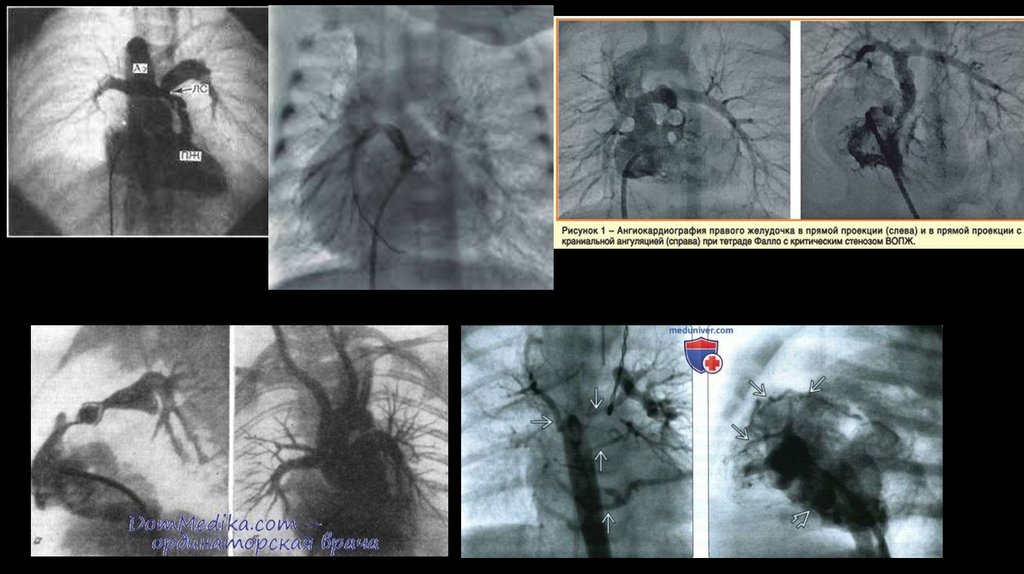

83. Ангиокардиография тетрады Фалло

Ангиокардиография тетрады Фалло